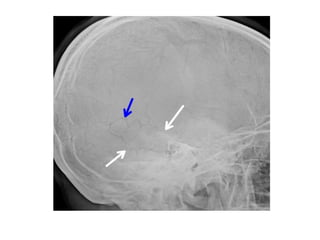

Frontal and lateral chest radiographs demonstrate an unusually-shaped (yellow arrow)

levopositioned (green arrow) heart. The heart is displaced upward from the left

hemidiaphragm (white arrow) and there is a clear space between the sternum and the

heart (blue arrow) on the lateral image.

Frontal and lateralchest radiographs demonstrate an unusually-shaped (yellow arrow) levopositioned (green arrow) heart. The heart is displaced upward from the left hemidiaphragm (white arrow) and there is a clear space between the sternum and the heart (blue arrow) on the lateral image.